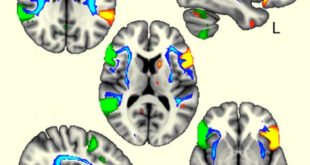

Read More »Scientists Identify Four Genetic Regions Associated with Left-Handedness

A team of researchers from the University of Oxford has identified four regions of the human genome associated with left-handedness in the general population and linked their effects with brain architecture. The language brain regions were more coordinated in left-handers between the two sides of the brain (in green and …